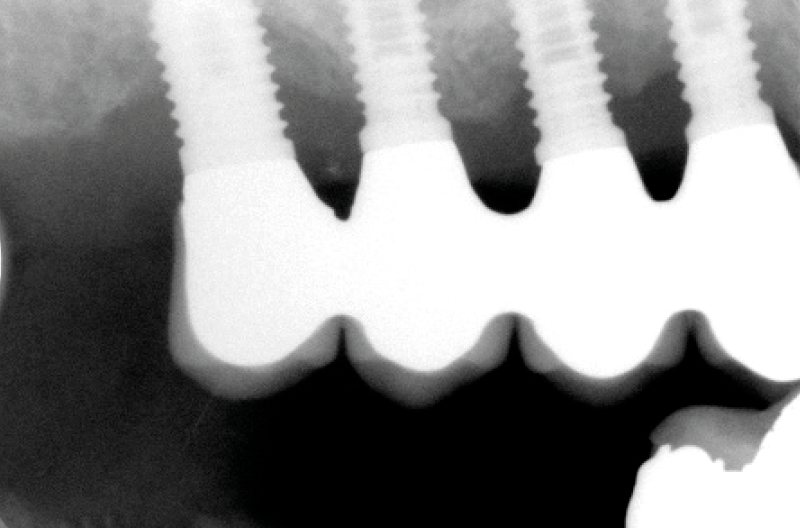

- Fig. 3 – Le radiografie endorali di fine trattamento evidenziano una incongruità della protesi, che appare sollevata nei settori posteriori.Tale condizione determina una impossibilità alla detersione a livello della connessione implant-abutment con conseguente accumulo di placca e compromissione dell’ampiezza biologica

- Figg. 4-7 – Le immagini Cross della TC evidenziano un non corretto posizionamento implantare; gli impianti non completamente inseriti dentro l’osso e troppo vestibolarizzati presentano spire esposte e questo contrasta la formazione di una stabile ampiezza biologica